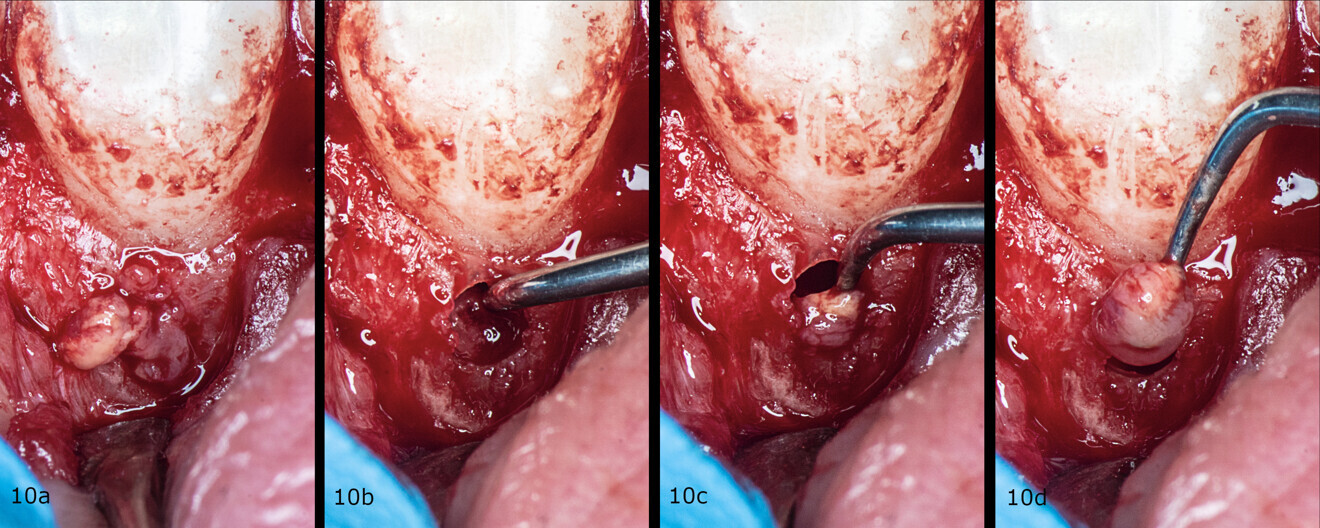

Figs. 10a–d: Removal of the granulation tissue step by step.

An incision was made from the maxillary left central incisor through the gingival sulcus to the right maxillary canine. After raising a flap, the granulation tissue was removed from the resorption cavity with a small excavator (Figs. 9–11). The root canal shaping protocol was performed with conventional chemomechanical preparation. The shaping sequence began with negotiation with passive hand files, followed by preparation with rotary files and irrigation using sodium hypochlorite with manual needle agitation. The irrigation protocol was performed as described in Case 1.